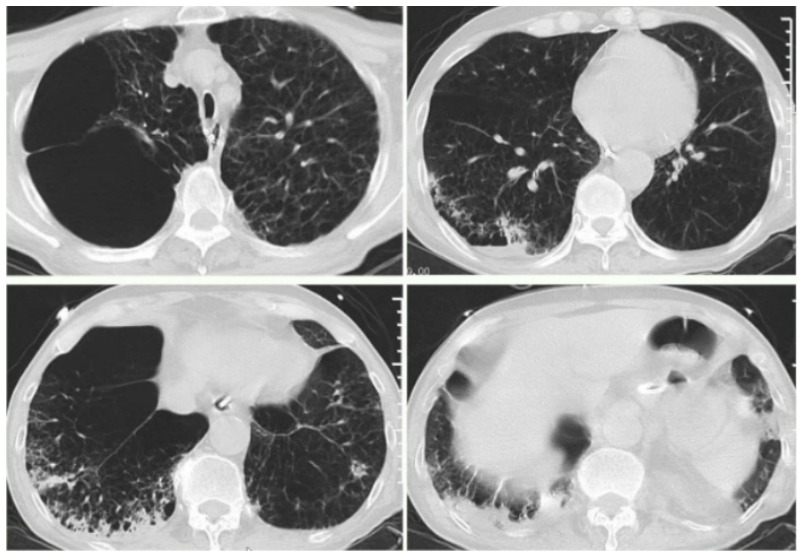

床旁支气管镜:隆突锐利,左右各叶支气管可见少量黏稠白色分泌物,予充分吸引,未见明显痰栓,各叶段予生理盐水肺泡灌洗,回收灌洗液(BALF),送检微生物培养。D-二聚体0.98 mg/L(胃内容物隐血阳性,预防性抗凝暂未实施,物理预防VTE)。考虑出现人机不协调可能是气道痉挛所致。调整呼吸机参数,更换为容量控制+压力支持模式,设定VT 为350 ml;加用阿曲库铵肌松;气道雾化治疗频率更换为q4h;甲泼尼龙剂量调整为40 mg q12h。调整后气道峰压下降至22 cmH2O。复查血气分析:pH 7.343,PaCO2 64.5 mmHg,PaO2 152 mmHg,氧合指数381 mmHg,乳酸1.5 mmol/L。患者呼气相延长好转,气促症状改善。2024年1月23日20:07,患者入院46 h,气促较前加重,哮鸣音明显,RASS评分-1分。复查血气分析:pH 7.206,PaCO2 104 mmHg,PaO2 59 mmHg,HCO3- 41.4 mmol/L,乳酸0.8 mmol/L。复查胸片:未见右侧新发气胸,左侧气胸未见进一步吸收,炎症不明显(图3)。予加深镇静镇痛。调整呼吸机参数为SIMV+PSV。1月23日22:04血气分析:pH 7.276,PaCO2 86.8 mmHg,PaO2 71.7 mmHg,HCO3- 40.4 mmol/L,乳酸1.3 mmol/L。1月24日09:34血气分析:pH 7.335,PaCO2 80 mmHg,PaO2 67.7 mmHg,HCO3- 40.1 mmol/L,乳酸1.3 mmol/L。(1)患者二氧化碳潴留反复加重的原因是什么?气道痉挛缓解困难的原因是什么?(2)并发气胸加重?——复查胸片可以排除这种可能。(3)并发肺栓塞?——D-二聚体基本正常,临床表现也无明显证据。1月24日BALF培养结果提示为烟曲霉。是否是致病菌?该患者危险因素符合:①慢性病基础(慢阻肺);②糖皮质激素应用史;③广谱抗生素应用史。不符合之处:①体温正常;②炎症指标正常;③胸部影像学未见新发感染征象;④外周血G试验/GM试验正常。1月24日加用伏立康唑片剂0.2 g q12h鼻饲,复查胃内容物隐血阴性,VTE评分5分(高危),根据体重调整剂量后加用依诺肝素3000 U预防性抗凝治疗。甲泼尼龙减量至40 mg qd,雾化减至q12h。继续有创呼吸机辅助通气,动态调整呼吸机参数,镇静镇痛,肌松。完善lgE、过敏原检测;动态复查胸片、血气分析、炎症指标。检查结果回示:IgE 37 lU/ml;吸入物+食入物过敏原阴性。1月26日复查血常规+hs-CRP:WBC 6.4×109/L,NEU% 92.0%,EOS% 0.0%,Hb 124 g/L,PLT 201×109/L,hs-CRP 9.24 mg/L。呼吸机参数:SIMV+PSV, PCV/PSV 20 cmH2O, PEEP 10 cmH2O, VT 200~500 ml。1月25日血气分析:pH 7.402,PaCO2 70.1 mmHg,PaO2 94.4 mmHg,氧合指数270 mmHg,乳酸1.1 mmol/L。1月26日血气分析:pH 7.431,PaCO2 67.7 mmHg,PaO2 80.5 mmHg,氧合指数230 mmHg,乳酸1.4 mmol/L。1月27日血气分析:pH 7.462,PaCO2 60.8 mmHg,PaO2 88.2 mmHg,氧合指数252 mmHg,乳酸1.6 mmol/L。1月27日复查胸片:与1月24日胸片对比,气胸未进一步加重,亦未见新发感染病灶(图4)。患者气道痉挛仍然存在,1月27日试停肌松后气道痉挛加重,人机不协调,脱机困难,1月29日出现发热(图5),气道内分泌物未见增多。抗感染药物已经覆盖了烟曲霉,患者为何出现发热症状——口服伏立康唑血药浓度不足?合并其他微生物感染?出现脓毒血症?寻找依据:查伏立康唑血药浓度为5.26 μg/ml(正常范围)。1月29日复查血常规:WBC 6.7×109/L,NEU% 89.3%,EOS% 0.0%,Hb 127 g/L,PLT 260×109/L,hs-CRP 3.66 mg/L。PCT、IL-6均正常,完善血培养【5~7天,等待结果】。经验性加强抗感染,停用哌拉西林他唑巴坦,更换为美罗培南。BALF送检NGS进一步明确致病菌。1月31日复查胸片:没有明显的新发感染迹象(图6)。送检BALF NGS 1天后结果回报:烟曲霉(序列数2272),乙型流感病毒(序列数47)。伏立康唑改为针剂0.2 g q12h,联合卡泊芬净50 mg qd(首剂70 mg),联合两性霉素B脂质体50 mg biw雾化;加用玛巴洛沙韦抗病毒。患者气道痉挛明显,气胸风险大,床边备胸膜切开包。复查血常规+hs-CRP:WBC 7.8×109/L,NEU% 86.6%,Hb 130 g/L,PLT 198×109/L,hs-CRP 1.0 mg/L。血培养回报阴性(双瓶双侧)【脓毒血症依据不足】。经过上述治疗,患者体温较前下降,支气管镜下气道分泌物较前减少,气道痉挛部分缓解,呼吸机参数改善,试停肌松。1月31日血气分析:pH 7.423,PaCO2 59.9 mmHg,PaO2 75 mmHg。2月1日血气分析:pH 7.420,PaCO2 58.6 mmHg,PaO2 81.2 mmHg。2月4日患者再次出现发热,体温最高38.1℃,气道痉挛加重,血气分析提示二氧化碳潴留加重,PaCO2 71.6 mmHg。复查炎症指标:WBC 12.2×109/L,NEU% 93.2%,hs-CRP 32.97 mg/L,PCT 0.068 ng/ml,IL-6 19.8 pg/ml。复查胸片提示两肺炎症改变,右肺下野团片影(图7)。复查BALF细菌培养:纹带棒状杆菌>103CFU/ml。真菌培养:无真菌生长。复测伏立康唑血药浓度3.03 μg/ml。纹带棒状杆菌是定植,还是致病?2月4日复查胸部CT:与入院时CT相比,出现两下肺斑片渗出影(图8)。考虑患者合并细菌感染。

图8 复查胸部CT(2024-02-04)